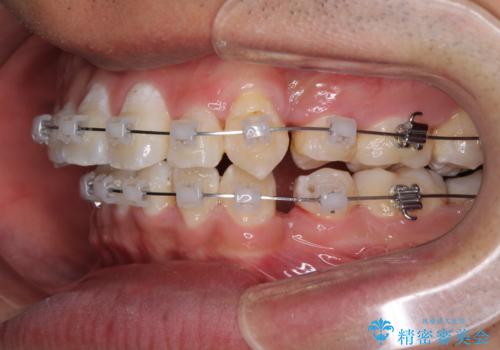

- クリアブラケット

- 前歯の叢生と八重歯を気にして来院された患者様です。

叢生が強く、奥歯の咬合も左右差が大きかったため、上下左右4本を抜歯して、ワイヤー矯正を行うこととしました。

奥歯の咬み合わせを改善したいため、治療期間が長くなりましたが、患者様には辛抱強くお付き合いいただきました。

上下の正中を合わせることもでき、患者様には大変満足していただきました。